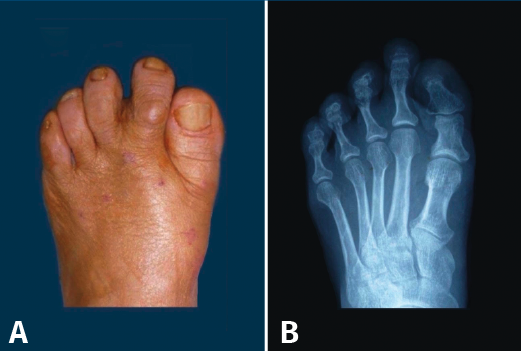

Figura 7. Neanderthal foot o pie ancestral de Dudley Morton. A: aspecto clínico; B: imagen radiológica.

En los primates arborícolas, existen pues a nivel del antepié una serie de características anatómicas también presentes en el HV en la especie humana: pronación del primer metatarsiano, ángulo I-II muy aumentado, hipermovilidad del primer radio y oblicuidad de la articulación cuneometatarsiana. Todas estas características son la justificación de la hipótesis de un factor atávico en muchos casos de HV.

Figura 11. Hallux valgus en una adolescente. A: radiografía del pie de la niña cuando tenía 4 años; B y C: aspecto clínico y radiológico a los 12 años de edad.

R. Miralles y N. A. Barnicot en un estudio llevado a cabo en Mozambique y Nigeria, en poblaciones que habitualmente no llevan ningún tipo de calzado(48,49), no encontraron HV. En Japón, las primeras publicaciones sobre HV aparecen después de la segunda guerra mundial, cuando las mujeres japonesas empiezan a utilizar calzado occidental(50). Recordemos también que existen HV congénitos aislados o que forman parte de una enfermedad generalizada como la fibrodisplasia osificante progresiva(51). En ocasiones, también podemos ver HV juveniles en adolescentes que nunca han llevado calzado estrecho por su parte anterior (Figura 11).